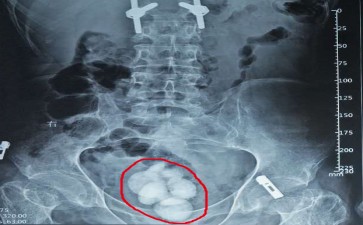

膀胱结石

膀胱,就像是我们身体里的一个“尿液蓄水池”,负责储存肾脏产生的尿液,等合适时机排出体外。而长春结石医院膀胱结石呢,就是在这个“蓄水池”里长出的“硬疙瘩”。它们有的是从肾脏“溜”下来,在膀胱里“安家落户”;有的则是在膀胱内直接形成,与尿液中的矿物质沉淀、感染等因素有关。

这“捣蛋精灵”一旦作祟,麻烦可不少。排尿时突然中断,就像播放电影时突然卡顿,让你尴尬又难受;下腹部和会阴部的疼痛,会随着结石的移动而加剧,让你坐立不安。更可怕的是,如果结石长期刺激膀胱黏膜,还可能引发感染,导致尿频、尿急、尿痛等症状,甚至引发膀胱癌,成为真正的“健康刺客”。

不过,对付长春结石医院膀胱结石,我们并非束手无策。多喝水能增加尿量,稀释尿液,减少结石形成,还能帮助小结石排出体外。对于较大的结石,可以通过体外冲击波碎石术或手术将其取出。预防长春结石医院膀胱结石,关键在于养成良好的生活习惯,多喝水、不憋尿、合理饮食。